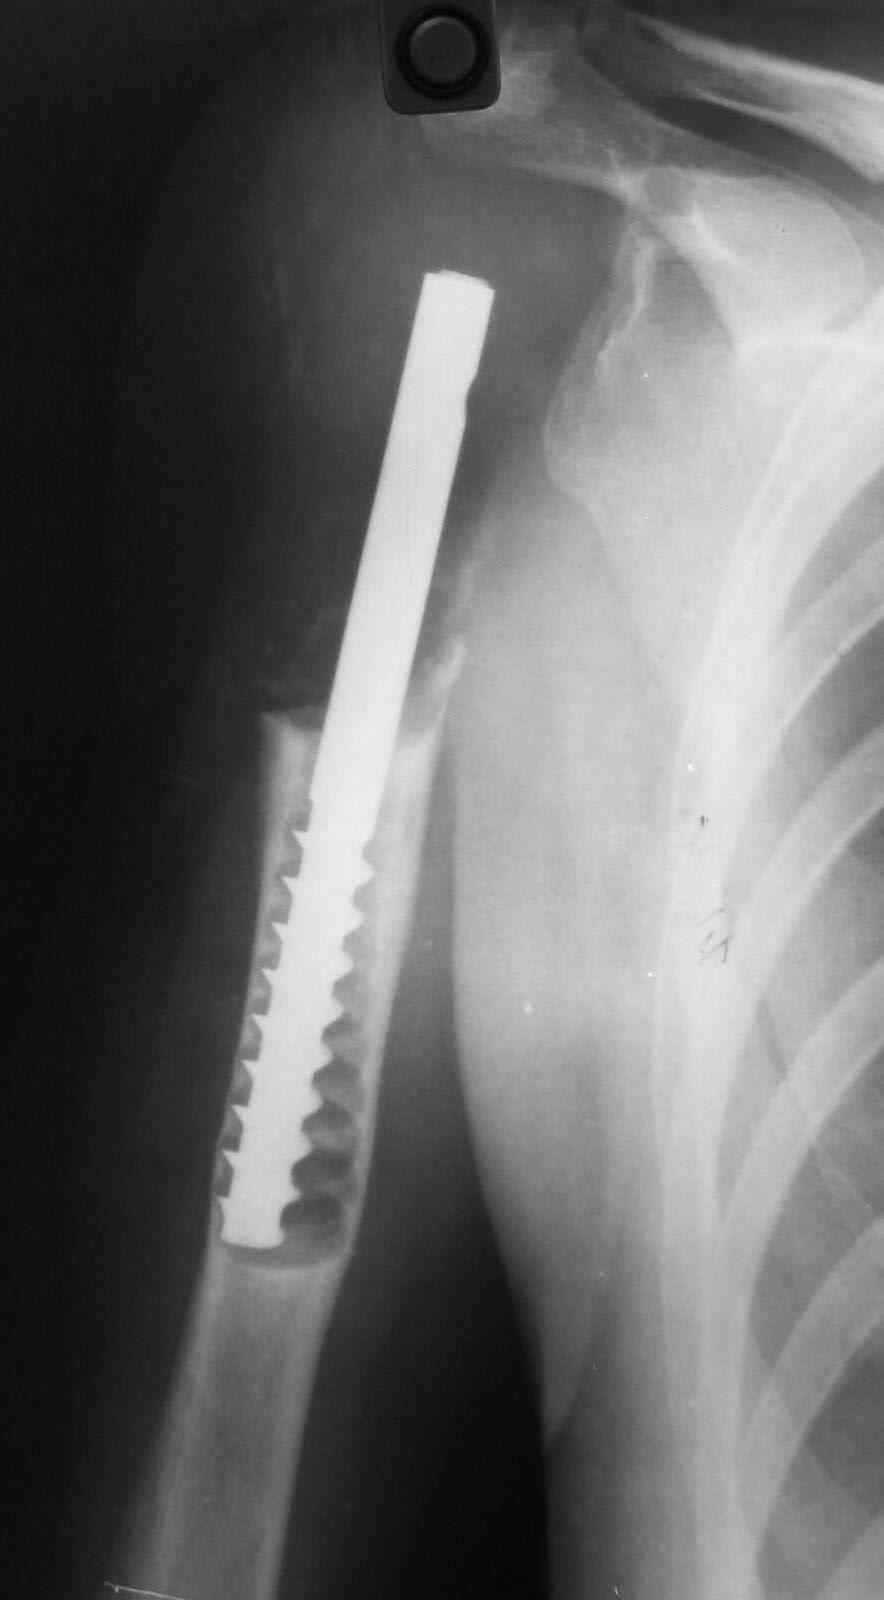

14 лет назад больной имлапнтирован протез плечевой кости выполненый по

методике Воронцова на штифте-штопоре Сиваша,за 2 года до имлапнатации

в онкологическом учереждении больной выполнена резекция проксимальоной

части плечевой кости по поводу ОБК, ксенотрансплантации головки, и

последующем его удалением на фоне гнойного процесса. У больной имелся

втянутый обширный рубец и болтающееся плечо, афункциональная верхняя

конечность, выраженный косметический дефект.П/опрационный период без

осложнений, сохранялась выраженная контрактура в плечевом суставе, но

стаилизация плеча и косметический эффект больную устраивал,даллее

контакт с больной был утерян (поменяла место жителсьтва. Через 14 лет

полноценной жизни сельской жешщины, больная нашла нас с клиникой

выраженной нестабильности протеза. Категорически отказалась от замены протеза.

Выполнена операция- малоинвазивно проведена LCP пластина в образованный канал над

головкой протеза, фиксирована к протезу и дистально к плечевой кости, на зоной резорбции

трепонирована кость, удалена соединительно-тканная оболочка, полость заполнена

chronOS. П/о период без осложнений, клиника нестабильности купирована. Прошло 2 года по

телефону сообщила, что у нее все хорошо, продолжает жить счастливой жизнью сельской

труженицы